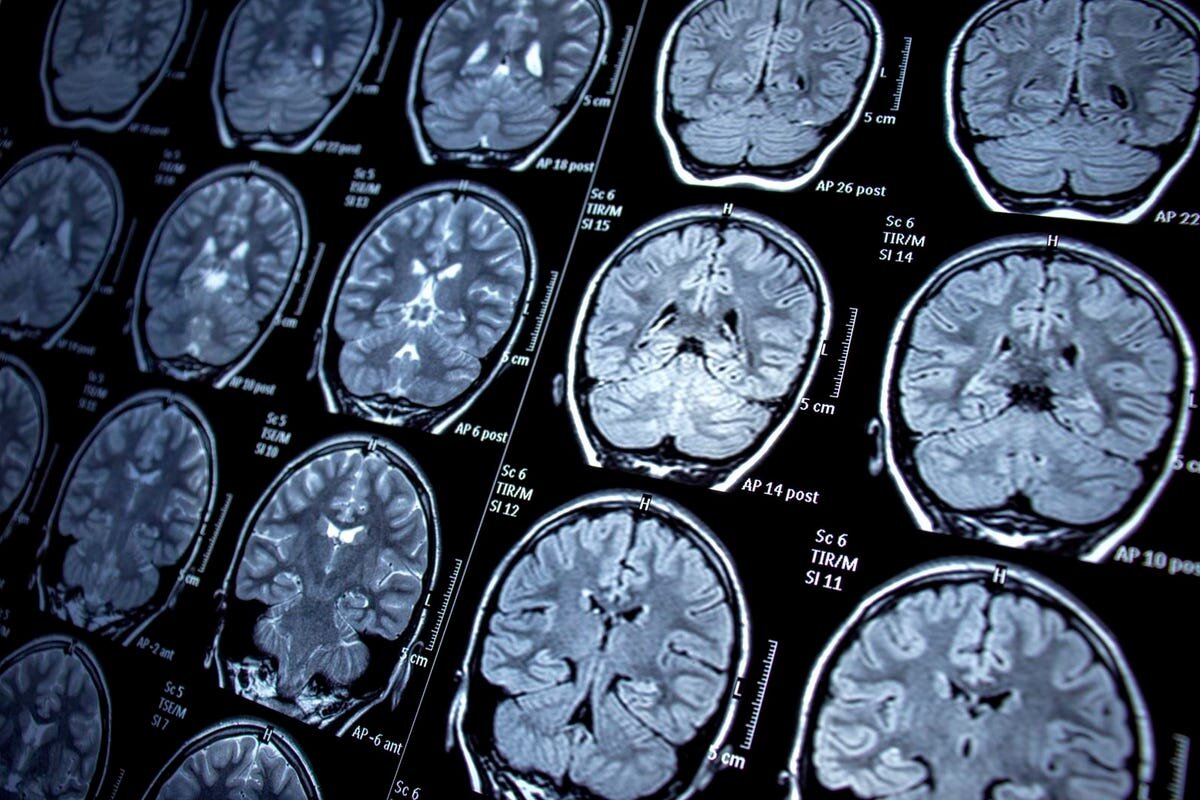

Магнитно-резонансная томография (МРТ) - это безопасное и распространенное метод исследования, который позволяет получить детальные изображения внутренних органов и тканей. Однако, если у вас есть татуировки, возникают определенные ограничения и риски при проведении МРТ.

МРТ работает на основе сильного магнитного поля, которое воздействует на атомы водорода в организме пациента. Татуировки, особенно те, которые содержат металлические чернила, могут содержать железо, медь или другие металлические элементы. При наличии металла в татуировках возникает риск искажения изображений, что может затруднить интерпретацию результатов МРТ.

Кроме того, магнитное поле МРТ может вызывать нагревание металлических частиц в татуировках, что может привести к ожогам или дискомфорту для пациента.